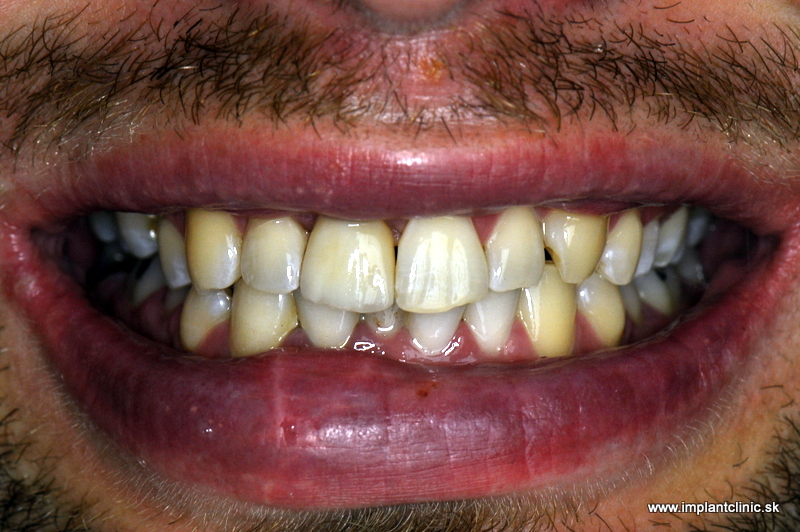

Prípadová Štúdia: Peter, 54 rokov, Bratislava

“Prišiel som o prednú dvojku po úraze. Bežný zubár mi navrhol mostík, ale to by znamenalo obrúsiť dva zdravé zuby. To som nechcel.”

Riešenie: Jeden implantát s keramickou korunkou

Výsledok: Po 6 mesiacoch má Peter zub, ktorý nerozoznáte od vlastných. Žiadne brúsenie. Žiadne kompromisy.

Cena: €1 350 (implantát + nadstavba + korunka)